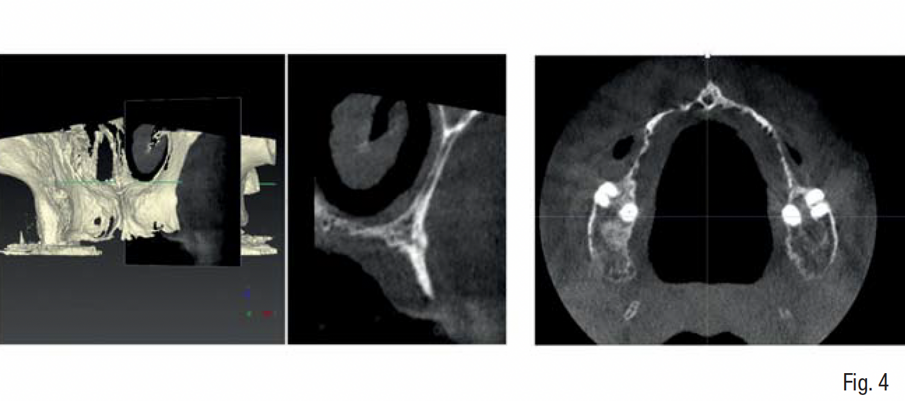

Gli esami radiologici di primo livello, quali la OPT, evidenziavano un’altezza ossea sufficiente al posizionamento implantare, ma la successiva analisi di secondo livello, quale la CBCT, evidenziava la presenza di una grave atrofia orizzontale a livello della regione edentula che rendeva impossibile la chirurgia implantare, oltre ad un quadro di sinusite mascellare cronica bilaterale. Su richiesta del paziente, si è deciso di mantenere i 2 molari sup. che sono stati trattati endodonticamente e successivamente protesizzati con 2 corone in zirconia; e di non eseguire il rialzo di seno mascellare bilaterale evitando l’iter terapeutico di approfondimento ORL.

In accordo con il paziente si decide di eseguire un intervento di rigenerazione ossea guidata (GBR) mediante una griglia in titanio customizzata e membrane riassorbibili (Figg. 2-4). Pertanto, 1 mese prima della chirurgia, è stato creato un modello osseo virtuale in formato .stl del mascellare sup. tramite segmentazione, a partire dai file .dicom della CBCT, utilizzando un software biomedicale dedicato (BTK- 3D, Biotec Srl, Dueville, Vicenza, Italy); è stato quindi eseguita la progettazione virtuale dell’aumento di volume osseo necessario per inserire gli impianti e la successiva progettazione della griglia customizzata al di sopra del volume aumentato; infine, è stata realizzata la griglia in titanio vera e propria mediante tecnologia di stampa 3D basata su sinterizzazione laser del titanio (3D-Mesh BTK, Biotec Srl, Dueville, Vicenza, Italy) (Figg. 5-8).